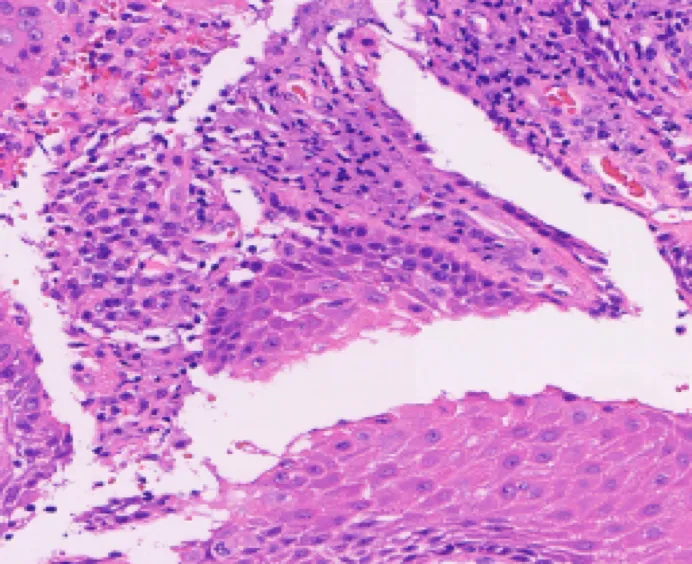

Artificial intelligence is applied based on Deep Convolutional Neural Networkd (DCNN) to retrospectively

analyze cervical liquid-based cytology samples to confirm its feasibility in clinical practice.

Whole-slide images annotation,

suspected cell detection model training

Efficient method to detect suspicious

cells in WSI, validate model with a large

number of slides

High sensitivity validated in clinical

practice for different lesion types

Graded lesion cells, count cell quantity

automatically

Whole-slide analysis, high TPR, slide

quality intelligent assessment